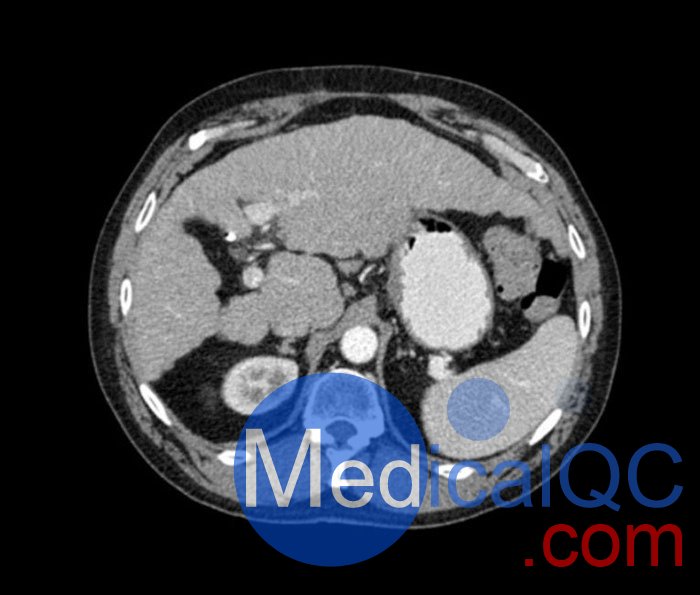

WEK53-04肝硬化腹部模體,WEK53-04門靜脈期腹部模體詳細(xì)介紹:

WEK53-04肝硬化腹部模體,WEK53-04腹部模體模擬了門靜脈期的造影劑增強(qiáng)腹部。它覆蓋了第十胸椎至第三腰椎。

WEK53-04肝硬化腹部模體,WEK53-04腹部模體代表膽囊切除術(shù)后的腹部,帶有小夾子。肝臟有肝硬化的典型體征,在第三腰椎水平植入下腔靜脈過濾器。兩個(gè)腎臟都有囊性病變,左側(cè)有一小塊腎結(jié)石。

該模型可用于 CT(包括 CBCT)以評(píng)估和優(yōu)化成像性能和后處理應(yīng)用,包括支持 AI 的應(yīng)用。它也適用于培訓(xùn)目的。

該模型提供了對(duì)軟組織和骨組織的詳細(xì)而逼真的模擬??障吨刑畛渲s-160HU的纖維素-聚合物復(fù)合材料。

WEK53-04肝硬化腹部模體,WEK53-04門靜脈期腹部模體診斷特征

真實(shí)模擬脈管系統(tǒng)、骨骼和軟組織,包括肝臟、胰腺、脾臟、腎上腺、腎臟、胃、小腸和結(jié)腸。

• 肝硬化

• 膽囊切除術(shù)

• 下腔靜脈濾器

• 腎囊腫

• 腎結(jié)石

• 淋巴結(jié)腫大

WEK53-04肝硬化腹部模體,WEK53-04門靜脈期腹部模體產(chǎn)品成像圖: